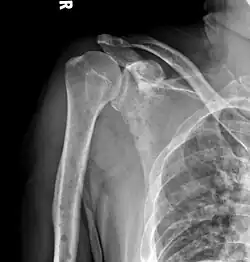

The diagnostic examination of a person with suspected multiple myeloma typically includes a skeletal survey. This is a series of X-rays of the skull, axial skeleton, and proximal long bones. Myeloma activity sometimes appears as "lytic lesions" (with local disappearance of normal bone due to resorption) or as "punched-out lesions" on the skull X-ray ("raindrop skull"). Lesions may also be sclerotic, which is seen as radiodense.[76] Overall, the radiodensity of myeloma is between −30 and 120 Hounsfield units (HU).[77] Magnetic resonance imaging is more sensitive than simple X-rays in the detection of lytic lesions. An MRI may supersede a skeletal survey, especially when vertebral disease is suspected. Occasionally, a CT scan is performed to measure the size of soft-tissue plasmacytomas. Nuclear Medicine Bone scans are typically not of any additional value in the workup of people with myeloma (no new bone formation; lytic lesions not well visualized on nuclear bone scan).

Skull X-ray showing multiple lucencies due to multiple myeloma -

Humerus with multiple myeloma lesions -

Same humerus before, with just subtle lesions